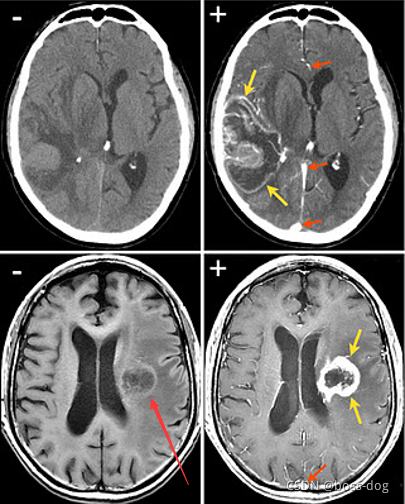

上图中使用了对比剂(通常是碘),可以增强肿瘤与正常脑组织的对比。如碘注射到血液中,在血管里面,可以吸收很多的X光,肿瘤这个部位因为血管多所以碘的含量高,可以吸收很多的X光,就被照亮了。